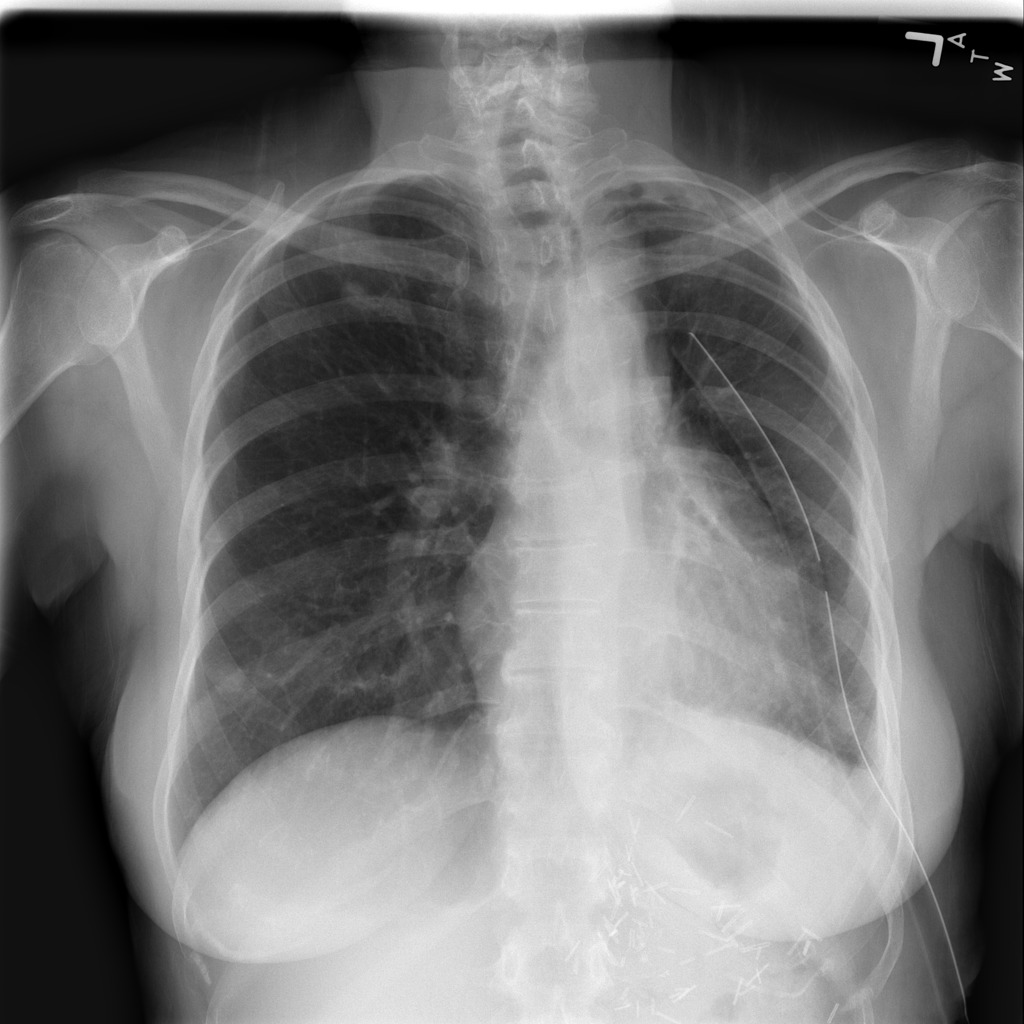

突然喘气,无缘无故地无助地呼吸,这会是肺衰竭吗?气胸可由胸部钝伤、肺部疾病的损害引起,有时候甚至无法探寻诱因。在某些情况下,肺萎陷可能会危及生命。气胸通常由胸部X射线放射科医生诊断,但有时很难确诊。因此由医学影像信息学学会(SIIM)提供了气胸图片数据,kaggle举办了一场比赛,开发模型,为非放射科医生提供更可靠的诊断,并在疾病早期识别气胸,挽救生命。

图片数据是胸透图片,并标注好了气胸区域。